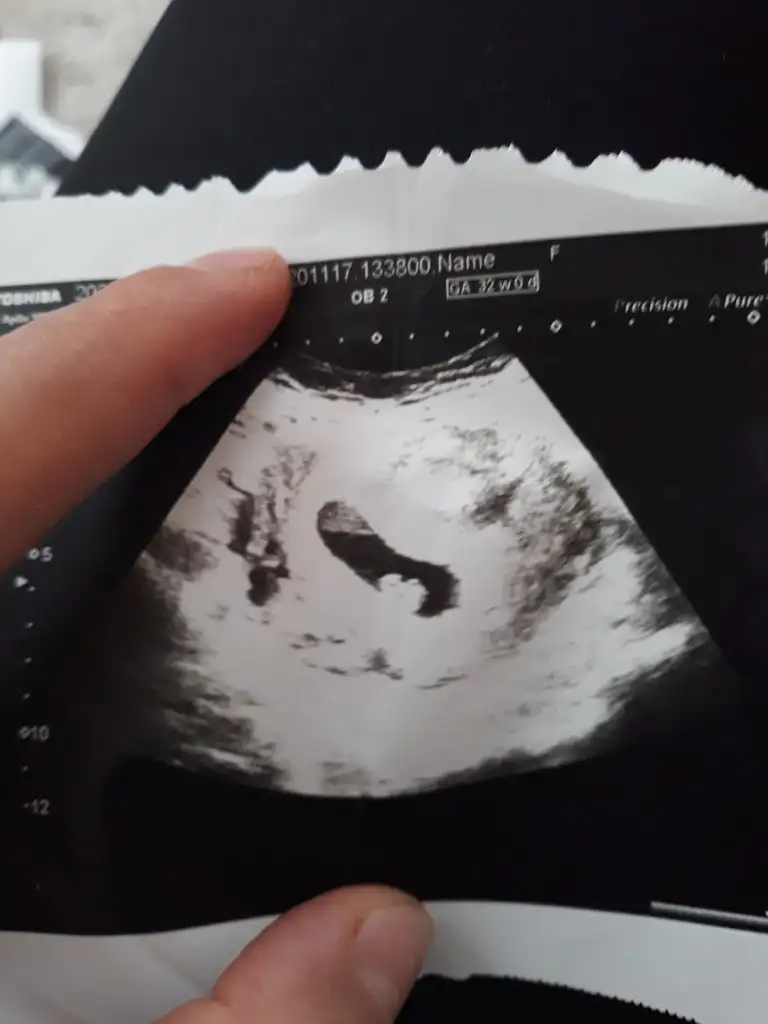

Ay, lütfen bana da yorum yapın karından 6+6 daylenki Ultrasonumuz

Eklentiler

• IMG_20210217_224509.webp

26,3 KB · Görüntüleme: 163